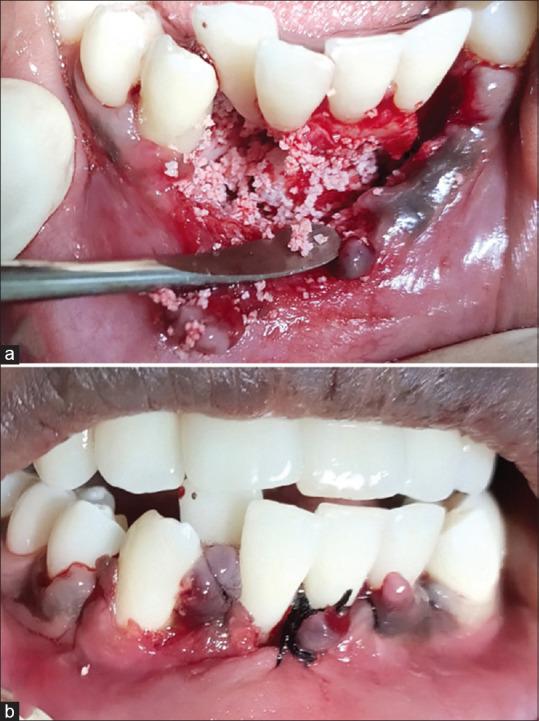

Gingival abscess is a localized, acute inflammatory lesion which is caused by various factors that include microbial plaque infection, foreign body impaction, and trauma. Management includes a simple incision and draining of the purulent exudate along with systemic antibiotics in most of the cases. This article reports a case of a 16-year-old female patient, with a chief complaint of painful and swollen gums in her lower right front tooth region of the jaw along with fever for the past 5 days. Emergency treatment of abscess drainage was done on day 1. On 5 day of review, the case presented with persistent signs of gingival inflammation in relation to 43 to 41. Considering the provisional diagnosis as dentigerous cyst with persistent gingival abscess, definitive treatment was performed by transalveolar extraction of the impacted canine and debridement of the osseous lesion. The histologic analysis of the lesion exhibited foci of eosinophilic coagulum-like areas with epicentric and radiating filamentous appearance at the periphery, which is suggestive of an inflamed dentigerous cyst with actinomycosis infection of periodontium.

牙龈脓肿是一种局限性急性炎症性病变,由多种因素引起,包括微生物菌斑感染、异物嵌塞和创伤。在大多数情况下,治疗包括简单的切开引流脓性渗出物以及全身性使用抗生素。本文报告了一例16岁女性患者,主要症状为下颌右下前牙区牙龈疼痛肿胀,伴有发热5天。第1天进行了脓肿引流的急诊治疗。复查第5天时,43至41区域仍有持续性牙龈炎症迹象。考虑初步诊断为含牙囊肿伴持续性牙龈脓肿,通过经牙槽拔除阻生尖牙并清除骨病变进行了确定性治疗。病变的组织学分析显示有嗜酸性凝块样区域,周边有中心和放射状丝状外观,提示为伴有放线菌感染的牙周炎的含牙囊肿炎症。